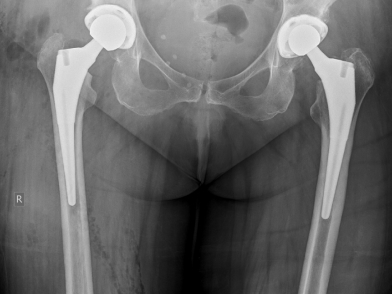

Ολική αρθροπλαστική και ημιαρθροπλαστική ισχίου

Υπάρχουν δύο κύριες κατηγορίες αρθροπλαστικής ισχίου: η ολική αρθροπλαστική και η ημιαρθοπλαστική. Η ολική αρθροπλαστική συνίσταται στην αντικατάσταση των αρθρικών επιφανειών τόσο της κοτύλης όσο και της μηριαίας κεφαλής από τις αντίστοιχες τους προθέσεις με την παρεμβολή ενός ένθετου (bearing surface – liner), το οποίο μαζί με την προσθετική μηριαία κεφαλή είναι σχεδιασμένο έτσι ώστε να εξασφαλίζει τις βέλτιστες τριβολογικές συνθήκες για την κίνηση της άρθρωσης. Ο συχνότερα χρησιμοποιούμενος τύπος ολικής αρθροπλαστικής ισχίου αποτελείται από ένα μεταλλικό κοτυλιαίο πρόθεμα με ένα πλαστικό (από πολυαιθυλένιο) ή κεραμικό ένθετο και ένα μεταλλικό μηριαίο πρόθεμα με μεταλλική ή κεραμική προσθετική κεφαλή. Στις μέρες μας, η εμπλοκή των προθεμάτων της αρθροπλαστικής με το οστό επιτυγχάνεται συνήθως μέσω τεχνικών χωρίς τσιμέντο (press-fit) με την περιστασιακή χρήση κάποιου κοχλία για ενίσχυση της προσθετικής κοτύλης. Η σταθεροποίηση με τη χρήση οστικού τσιμέντου είναι επίσης δυνατή ή και προτιμητέα σε ορισμένες περιπτώσεις, όπως είναι το εξαιρετικά οστεοπορωτικό οστό ή μετά από ακτινοθεραπεία. Άλλες επιλογές ολικής αρθροπλαστικής ισχίου περιλαμβάνουν τη χρήση διπλής κίνησης ή ακόμα και περιοριστικών ενθέτων.

Η ημιαρθροπλαστική ισχίου, από την άλλη πλευρά, περιλαμβάνει την εμφύτευση ενός μηριαίου προθέματος είτε με, είτε χωρίς τσιμέντο, και στις περισσότερες περιπτώσεις μία διπολική προσθετική κεφαλή, η οποία αποτελείται από μία μικρή μεταλλική κεφαλη που περικλείεται από ένα μεγαλύτερο μεταλλικό κυπέλλιο, τα οποία λειτουργούν σαν ενιαία μονάδα. Η αρθρική επιφάνεια της κοτύλης δεν αντικαθίσταται σε αυτή την τεχνική, οπότε η προσθετική κεφαλή αρθρώνεται απευθείας με την γηγενή κοτύλη με τα δύο συστατικά της πρώτης να ολισθαίνουν και να περιστρέφονται συγχρονισμένα μέσα στην τελευταία.